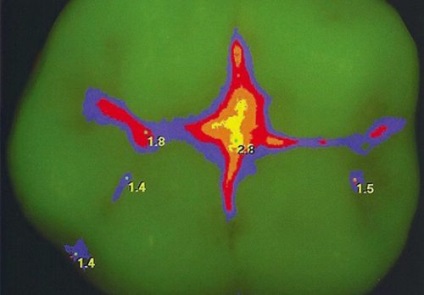

A fogszuvasodás Marker lehetővé teszi érzékelni még láthatatlan fogszuvasodás

- Azonosítására hasadék szuvasodás van egy speciális egység lézer fluoreszcencia. Ez a leghatékonyabb módszer a diagnózis a fogszuvasodás, mivel lehetséges, hogy azonosítsa a betegség szinte minden szakaszában. A hátránya ennek a diagnosztikai módszer a magas ár, ezért engedheti meg magának, hogy azúrkék fluoreszcencia az állam, nem minden ember.

Laser fluoreszcencia repedések - lumineszcencia csökkenési